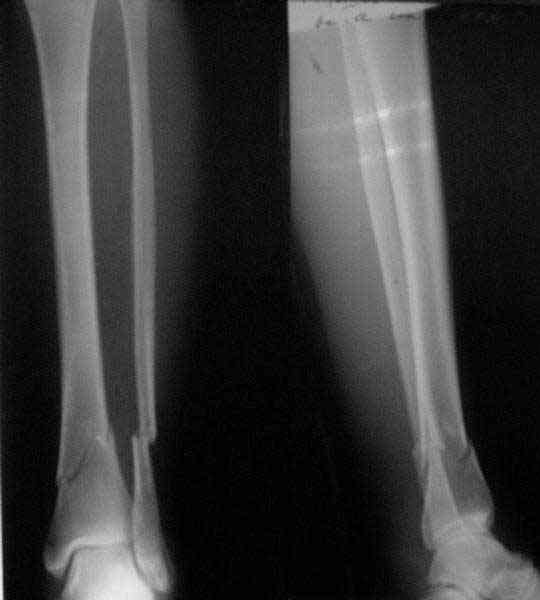

There are some more tricks which allow not to plate the fibula and provide good alignment and stability. A small wire distractor can provide alignment and restore length of both tibia and

fibula. Angular stability of the tibia is provided by insertion of more than two conventional medial-lateral locking screws. To maintain the position of the fibula perQ insertion of a single position screw often could be enough. I bet the articles didn't analyze the options.

A typical case is attached, also an image with intra-op reduction obtained by a small wire distractor, in the moment of insertion a Poller wire in AP direction. Fixation by a SIGN nail. Despite the fibula was not fixed healing was obtained with the unchanged alignment.

In delayed cases acute length restoration performed only in the tibia may leave the fibula shortened thus change the mortise. So it is reasonable to restore length of both bones simultaneously by distractor and fix the fibula not with open reduction and plating but just by a single perQ screw. Example attached.